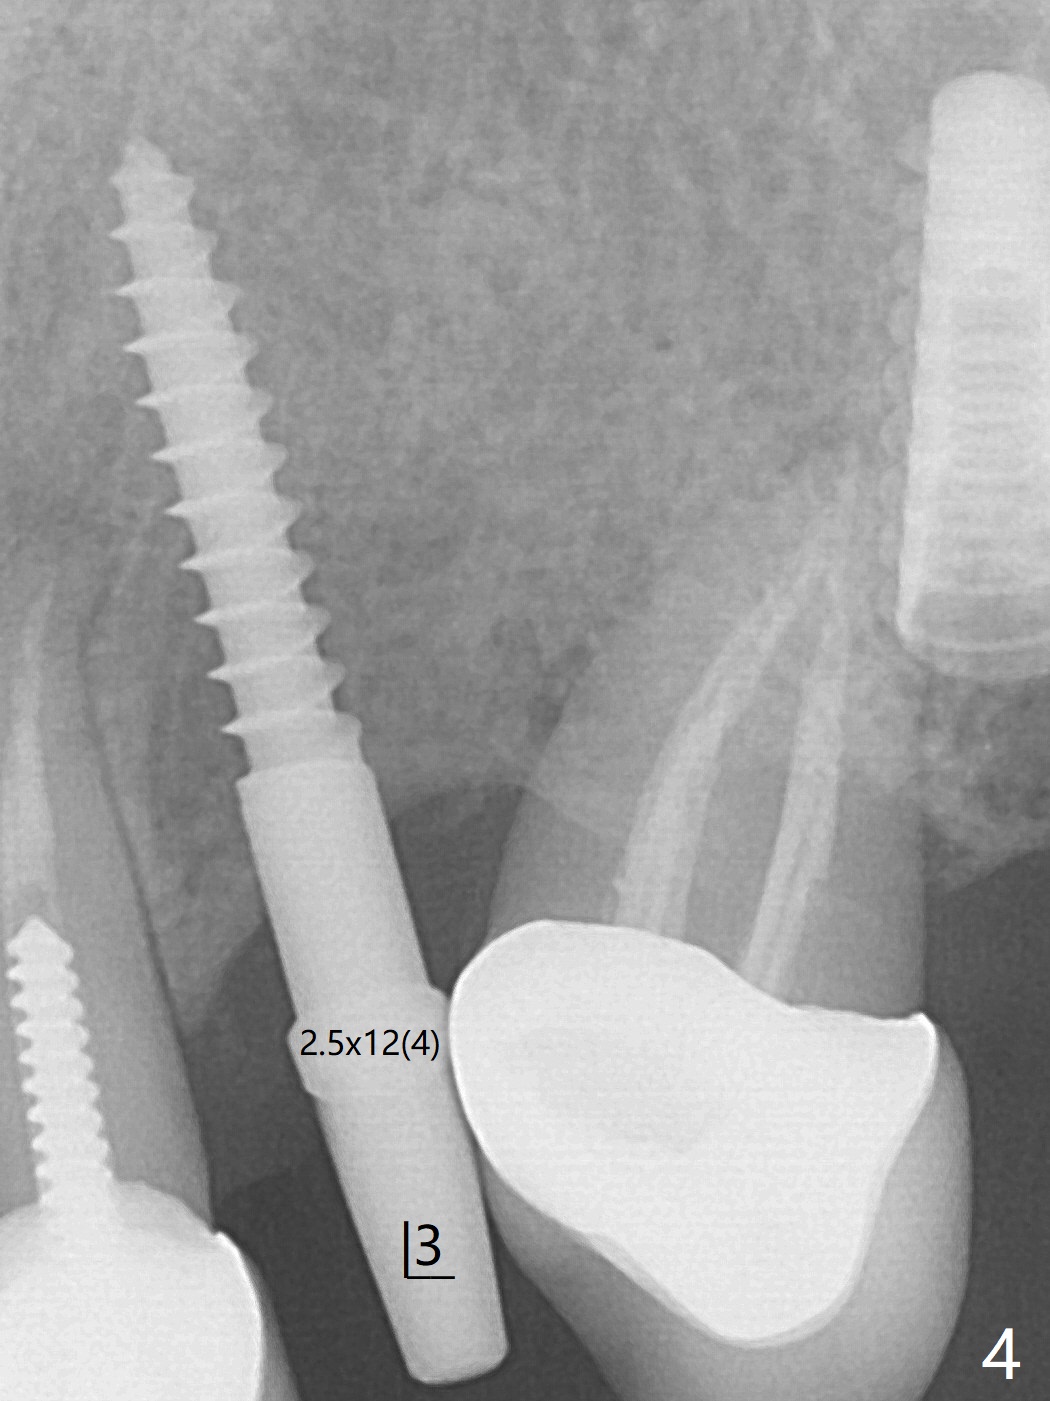

害怕病人局麻药很慢起效,术中身体会动,术中决定减小右下6,7植体直径0.5毫米(与导板设计相比),一旦植体越过牙槽嵴顶骨皮质,稳定性突然减低(图一)。尽管扭力10-15Ncm,为了避免二期手术,放置愈合基台(图二),6基台没有就位(箭头),因为植体种太深了,牙槽骨阻挡(*)基台就位。当取出6基台时,植体一起旋出,重新植入时,就没有种那么深(图三:箭头,与图一,二对比)。由于扭力低,只好放置愈合帽,骨粉(*),GEM Cap(6-9月胶原膜)和牙周胶水。由于导板设计缘故,左上5拔除,种植后,才开始左上3一段式植体植入(图四),5也植入太深(图五),必须放置最小直径最长袖(cuff)的基台(图六),今后导板即刻植牙先不要到达设计深度。术后一周CT显示尖牙植体位于牙槽骨内(图七 (>:腭侧牙槽嵴))。Bone graft fills in the buccal apical defect at #13 one week postop (Fig.8 <). 术后两个月左上3临时牙冠折裂,5松动(图九,十),后者取出衬里,软组织愈合。术后8个月左上3,5取模,右下6 uncover,愈合帽表面覆盖骨质,把7号牙愈合基台放到6号牙上,而7号牙放置4.5x4(4)毫米修复基台,固定牙周敷料,这样6号牙伤口不必缝合。术后8.5个月右下6放置4.5x7.5(4)毫米基台,发现7基台没有就位(图十一:箭头),通过旋转7 基台,终于就位(图十二),螺丝往下移位(与图十一:横线对比),但是基台边缘太低,不利于取模。改用5.5x4(5)毫米UF基台,临床上不能就位,局麻使用5.5毫米Profile Drill后,才能就位(图十三),螺丝下端超越最低螺沟(横线)。